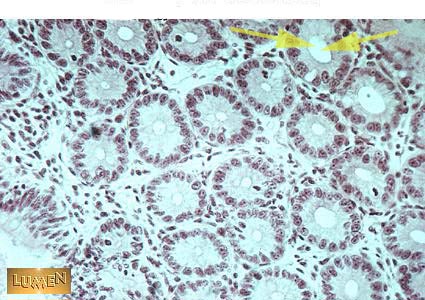

The arrow is in the lumen of what?

crypt